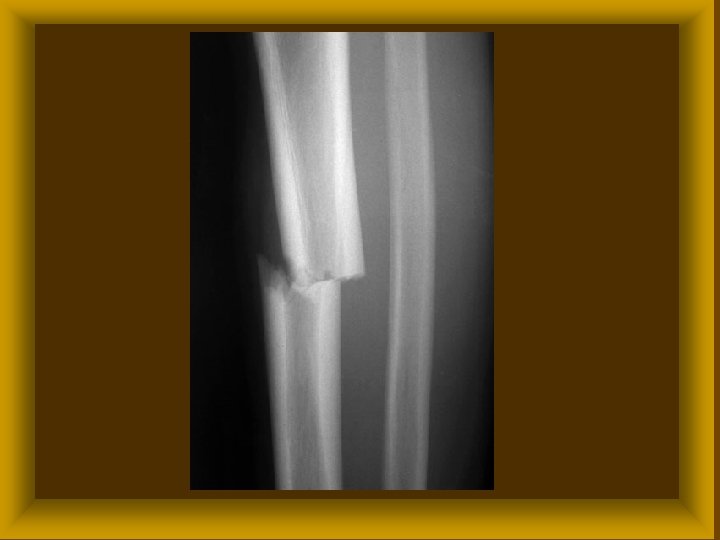

FRACTURÁK MORPHOLÓGIÁJA II Törési sík alapján : * haránt * hosszirányú * ferde * spirális Ø Törési darabok alapján * egyszerű * többszörös * rom törés Ø

FRACTURÁK MORPHOLÓGIÁJA III Ø Fractura sine dislocatione Ø Fractura cum dislocatione * ad longitudinem * ad latus * ad axim * ad periferiam

FRACTURÁK MORPHOLÓGIÁJA I ØRészleges törés * repedés ( fissura ) * megtöretés (infractio) ØTeljes törés